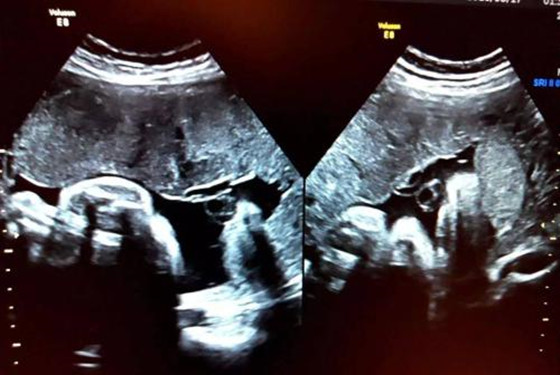

那么,怎样判断胎盘是否老化呢?我们可以通过看胎盘级别是否超过妊娠月份来判断,一般来讲,越临近足月的宝宝,胎盘成熟度多为2-3级,如果在怀孕20周时,胎盘成熟度已经达到2级的话,证明胎盘功能减退了;还有就是通过B超检查钙化点来判断,通过B超医生能够准确的看到胎盘上的钙化点,举个例子来说吧,钙化点散开的就诊断为2级,钙化点连成片的就断为3级。因此,大家在确诊胎盘是否老化时,最好找比较有经验的医生帮忙看,这样才能确保检查结果的准确性。